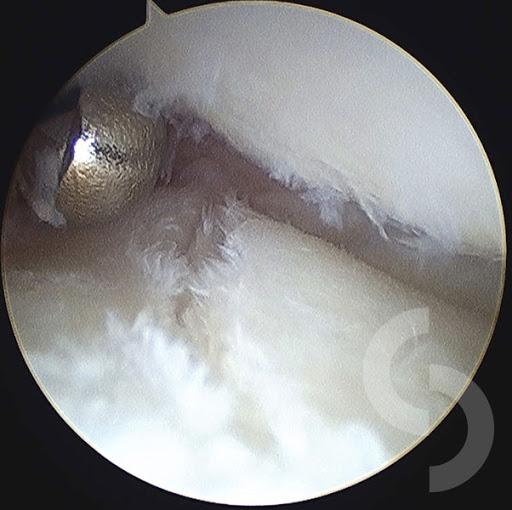

ΑΘΛΗΤΙΚΕΣ ΚΑΚΩΣΕΙΣ:

Αρθροσκόπηση γόνατοςΡήξη μηνίσκουΡήξη χιαστούΑρθροσκόπηση ώμουΡήξη τενοντίου πετάλουΑκρωμιοπλαστικήΑρθροσκόπηση ποδοκνημικήςΑρθροσκόπηση Αγκώνα - Πηχεοκαρπικής

Συγκεκριμένα αναλαμβάνει περιστατικά παθολογίας όπως σκολίωση, αυχενικό σύνδρομο, σπονδυλική στένωση, τενοντίτιδες, αθλητικές κακώσεις, πλατυποδία, άκανθα πτέρνας, οστεοπόρωση κ.α.,χειρουργικές επεμβάσεις όπως διαδερμική χειρουργική, μεταταρσαλγία, βλαισό δάκτυλο, γαμψοδακτυλία, νευρίνωμα Μόρτον, πτώση μεταταρσίων, οστεοαρθρίτιδα, αρθροπλαστική γόνατος, αρθροπλαστική ισχίου, αρθροσκόπηση γόνατος, ρήξη χιαστού, ρήξη μηνίσκου, αρθροσκόπηση ώμου, σύνδρομο καρπιαίου σωλήνα κ.α.